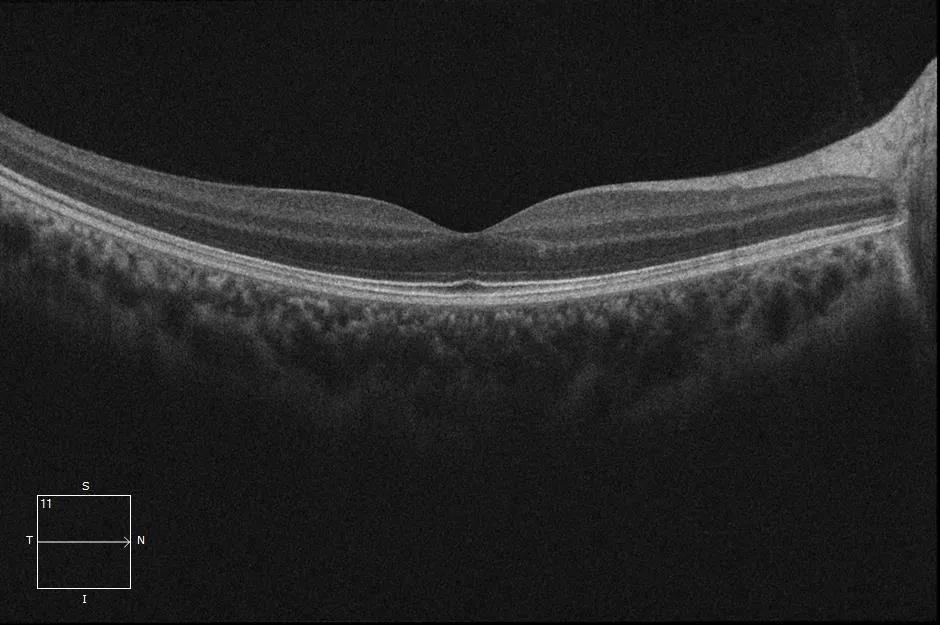

眼底图片

5月15日上午,许院长为鲍先生复查了术眼,并测量了术后视力,结果显示恢复良好。这让鲍先生意外的开心,原本手术前谈完话后,他只抱着保留现有视力不在下降的心态,而今天的结果却令他格外惊喜。